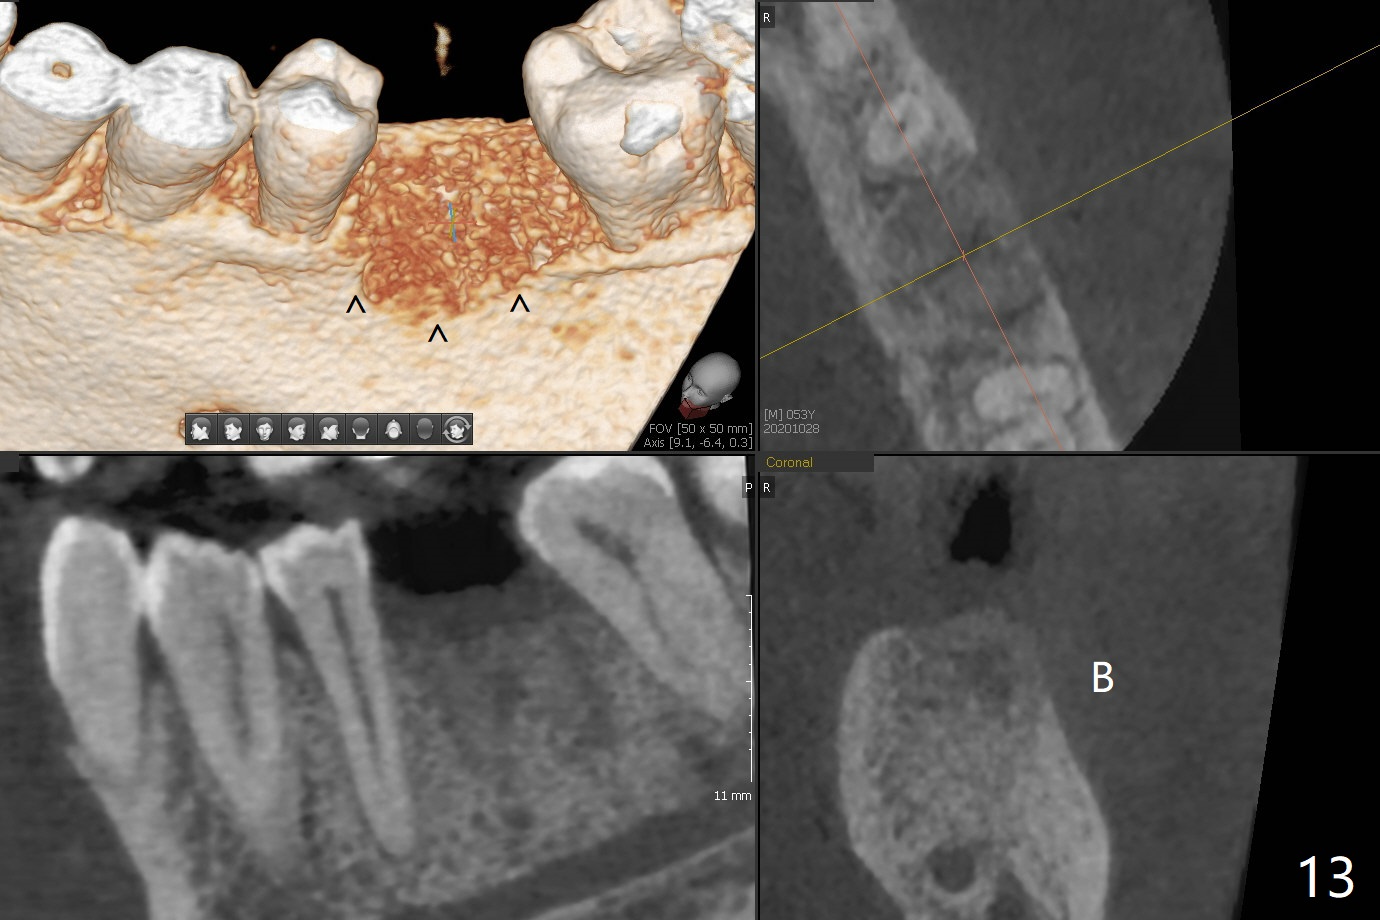

When the patient returns for #15 comp, the bone resorption and swelling at #19 are worse than those 3 years ago (Fig.1,2). After debridement, the mesial socket is large, while the septum is thin, irregular and with undercut (Fig.3). It seems difficult to obtain primary stability for an immediate implant. Vanilla bone and cortical bone hydrated with GEM21 S are placed for socket preservation (Fig.4,5), followed by 12x12 mm BioXclude and 4/0 PGA. In fact the bone height is limited for an immediate implant (Fig.6 (5x10 mm)). There is not enough bone in the septum for primary stability (Fig.7 (cross section of 3D image; L: lingual)). The socket heals 16 days postop (Fig.8). It appears that the granulation tissue is covered by a thin layer of granulation tissue (Fig.9 *), while the membrane remains in place (M). In fact the bone graft remains in the soft tissue zone as well as the hard tissue one (Fig.10). In spite of no apparent loss of bone graft (Fig.4,10), the graft seems to shrink in height 3.5 months postop (Fig.11), while the crest decreases (compare Fig.1 and 11). The keratinized gingiva is wide, but the alveolus reduces in width (Fig.12). The buccal crestal bone is lost 3.5 months postop (Fig.13).